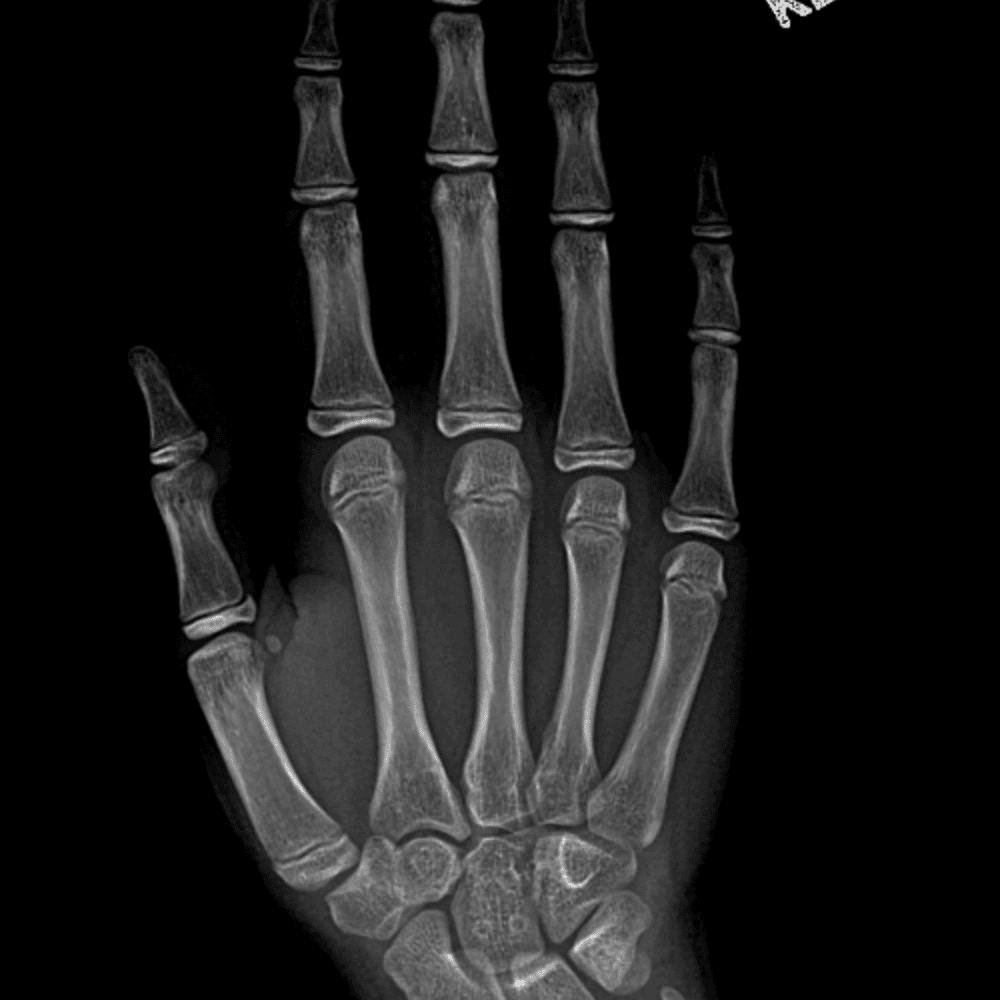

Simulates call by including subtle or difficult cases and some normals.

30 cases